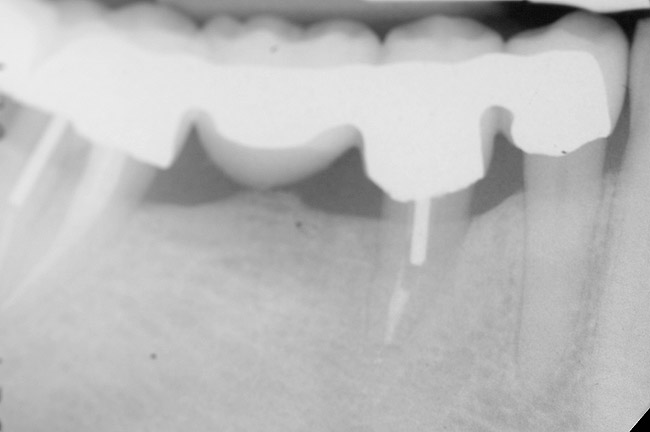

Figure 9 shows the implant placement at the time of extraction and Figure 10 shows the implant-supported fixed bridge. In one surgical procedure, the implants in the Nos. 29 and 31 positions were placed at the time of the extraction of these two teeth. The implants were restored approximately 3 months after placement.

Figure 9  Extraction of teeth Nos. 29 and 31 with immediate implants (Straumann USA, Waltham, MA) placed into the site.

Figure 9

Figure 10  Implants seen in Figure 9 restored approximately 3 months after placement.

Figure 10